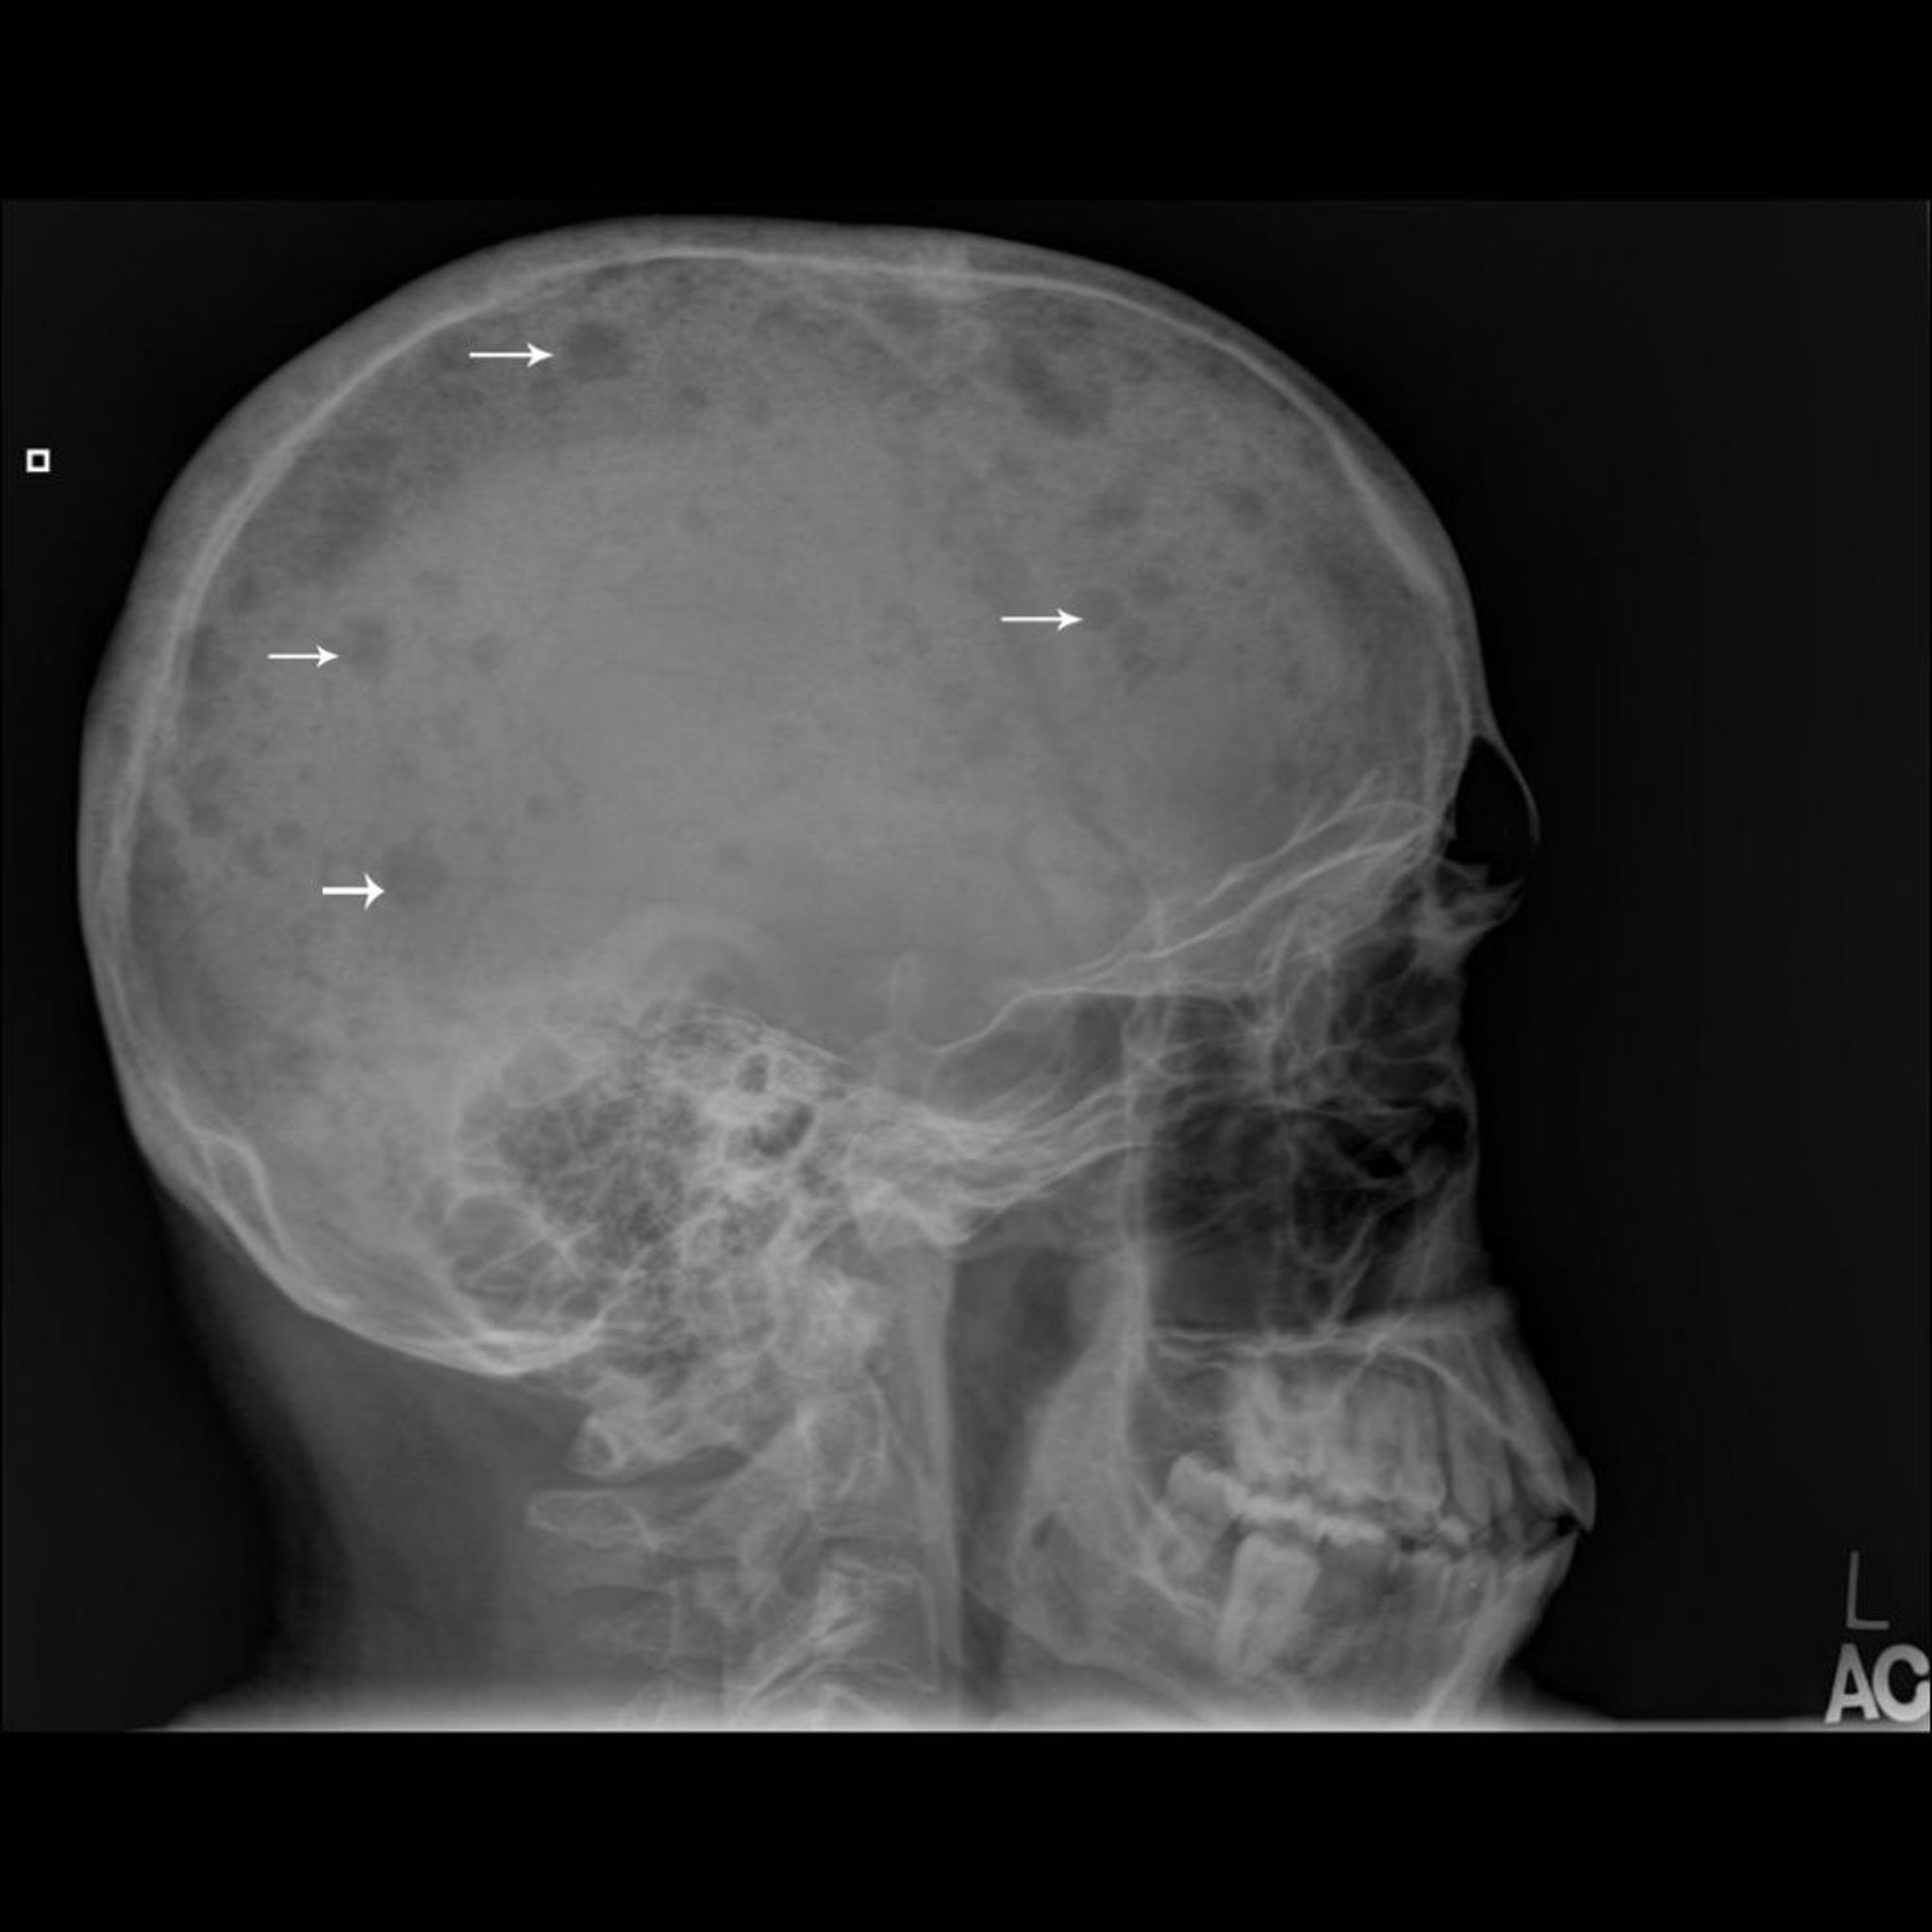

Myélome multiple

Cette radiographie du crâne montre plusieurs zones qui apparaissent comme perforées au niveau de l’os (flèches), caractéristiques du myélome multiple.

Image publiée avec l’aimable autorisation des Drs Michael J. Joyce et Hakan Ilaslan.